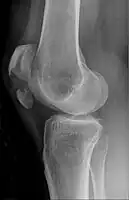

- Transverse fracture of patella

The patella can break in various ways depending on the way it is injured, and into two or more pieces.[1] Types include transverse, with one fracture line and is the most common type,[5] marginal, osteochondral and the rare vertical type, or stellate, where a direct compression force gives rise to a comminuted pattern.[5][7] Patella fractures can be further classified as displaced, where the broken ends of bone do not line up correctly and separate by more than 2mm, or undisplaced and stable where pieces of bone remain in contact with each other.[1][7] If fragments of patella bone stick out from the skin it is known as an open patella fracture, and closed if the overlying skin is intact.[1]